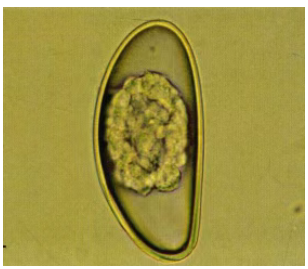

在分类学上与缩小膜壳绦虫一致,寄生于啮齿动物和人类小肠,也是人畜共患寄生虫,此虫感染人类较为常见。生活史与缩小膜壳绦虫一致,但摄入微小膜壳绦虫虫卵也可以直接被感染,是唯一不需要中间宿主即可完成整个生活史的绦虫,且虫卵可在环境中存活长达10天。虫卵呈椭圆形,大小为(48~60)um×(36~48)um,卵壳很薄,其内有较厚的胚膜,与缩小膜壳绦虫虫卵的形态区别在于胚膜两端略凸起并由该处各发出4-8根丝状物,弯曲地延伸在卵壳和胚膜之间,胚膜内含有六钩蚴。

微小膜壳绦虫虫卵(40×)